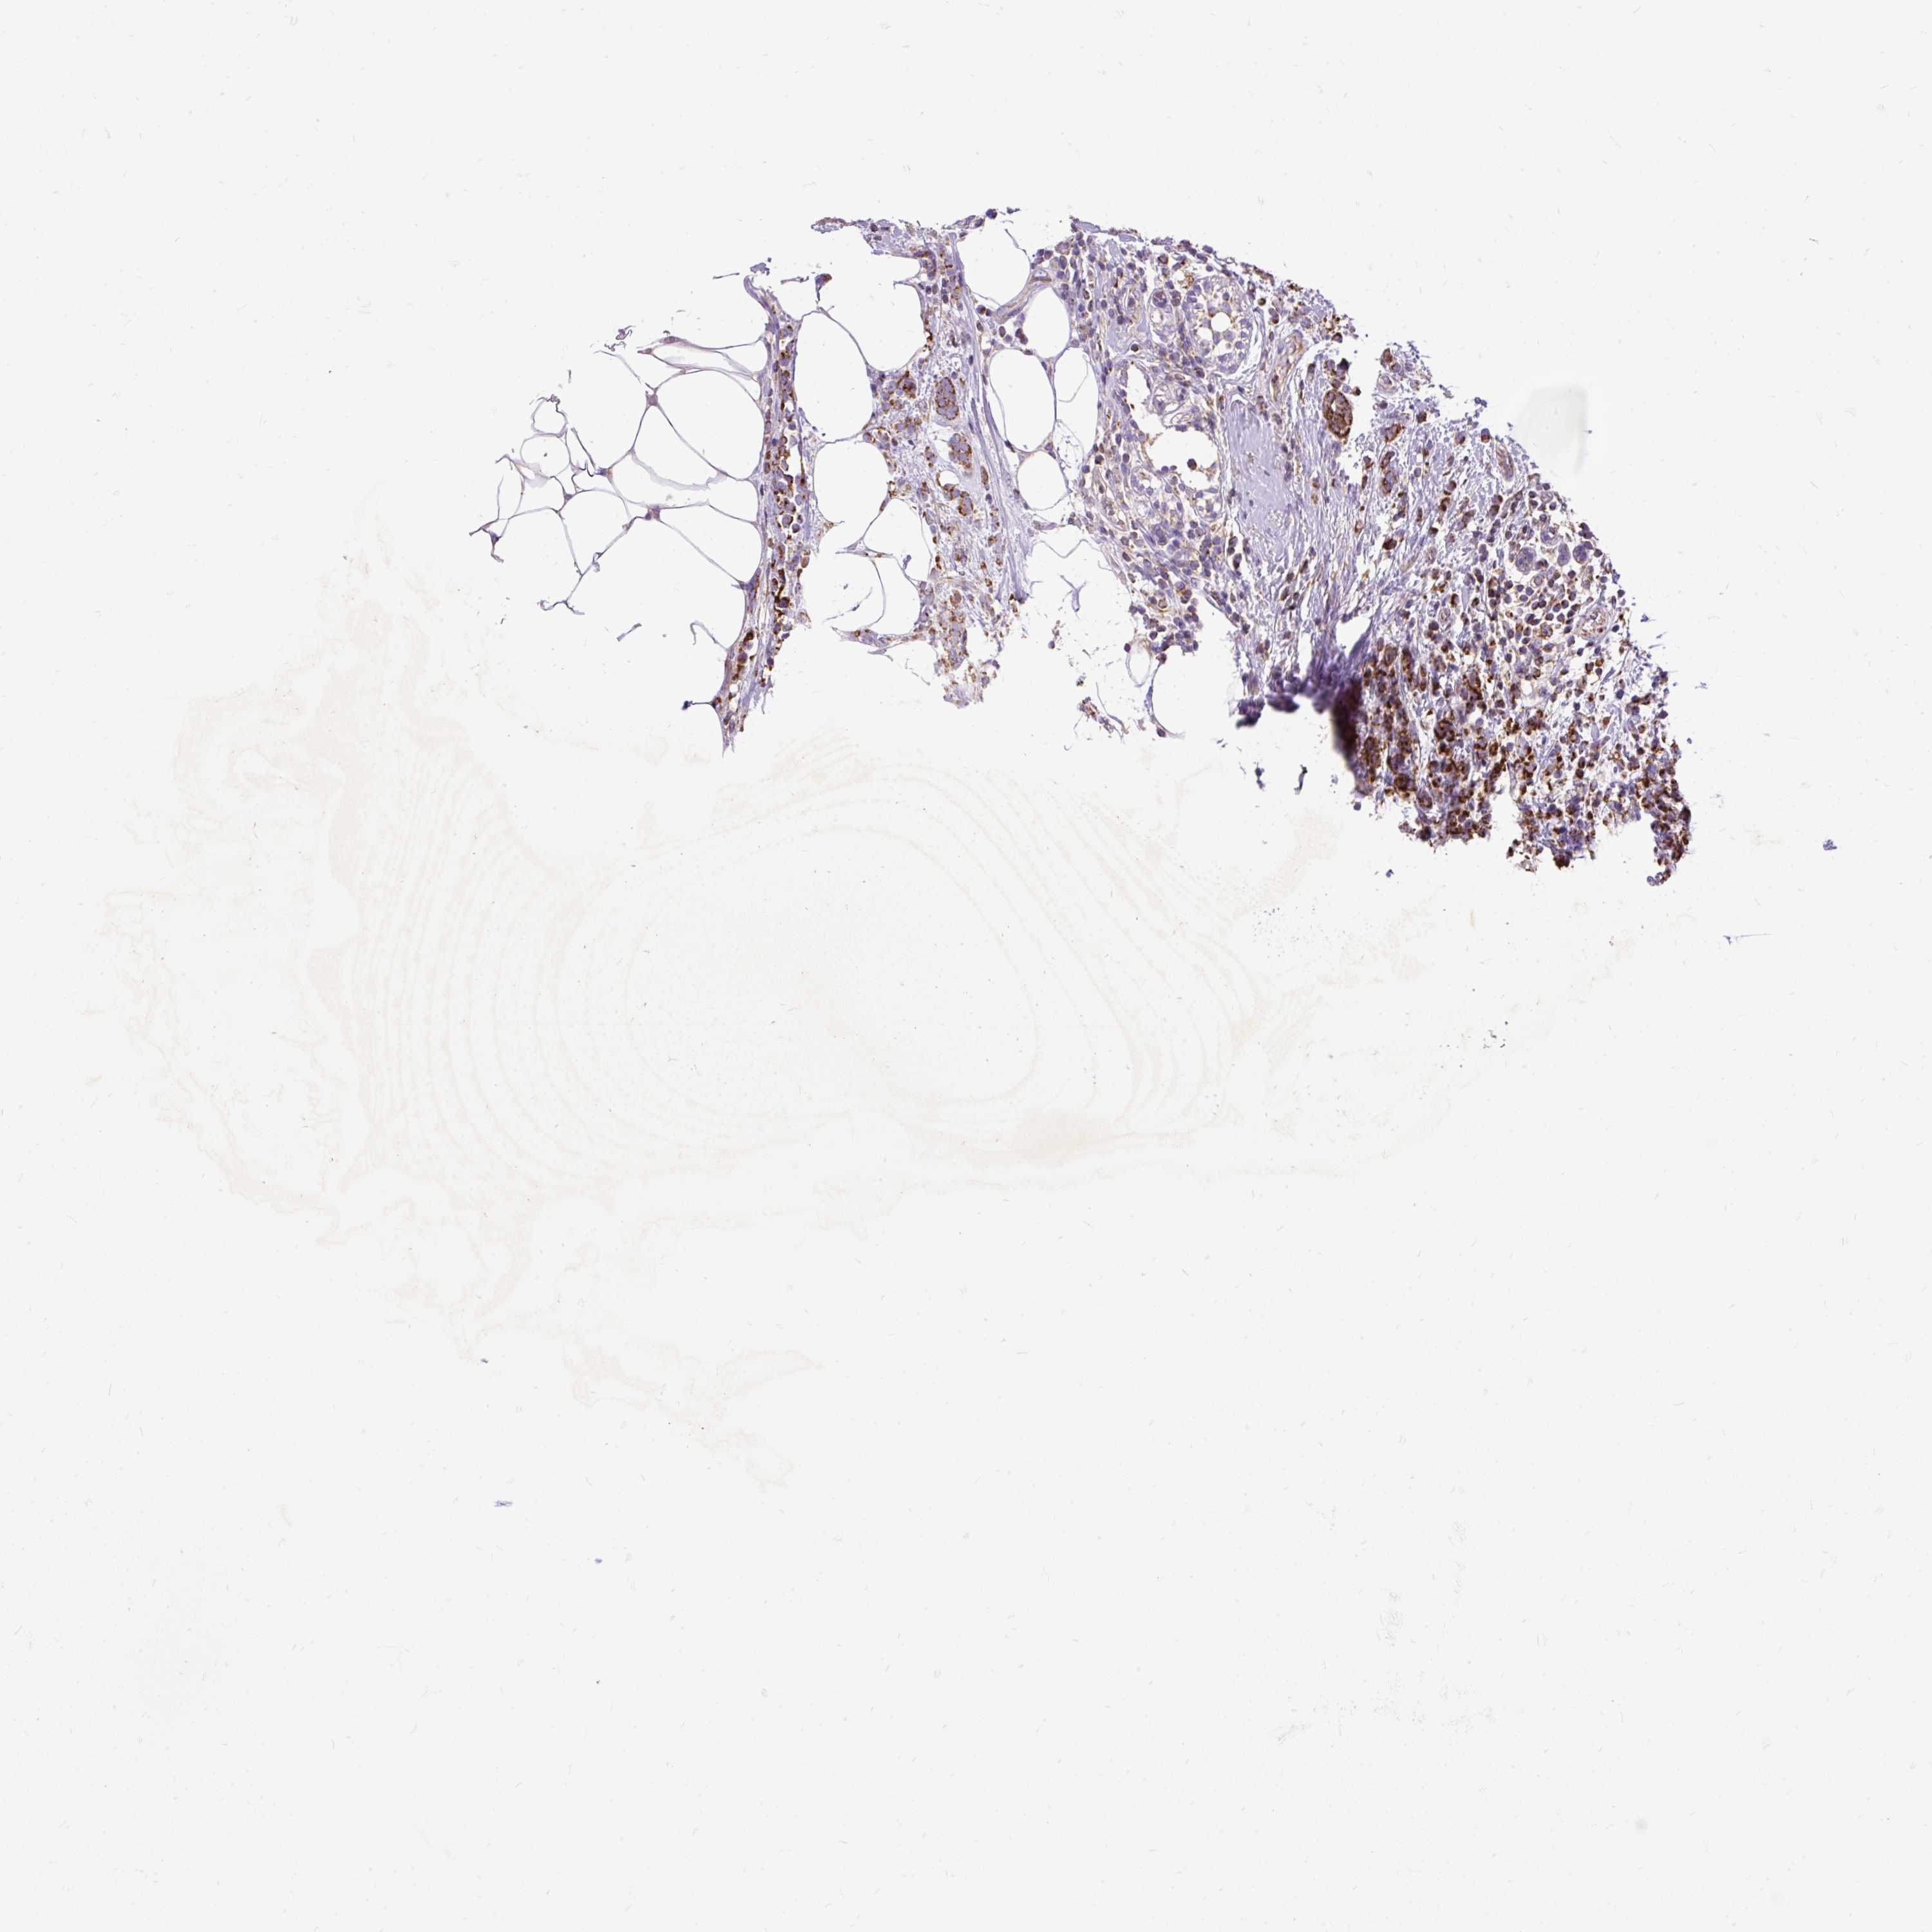

BRCA TCGA BRCA VALIDATION PROTEIN EXPRESSION

ANTIBODIES

AND

VALIDATION